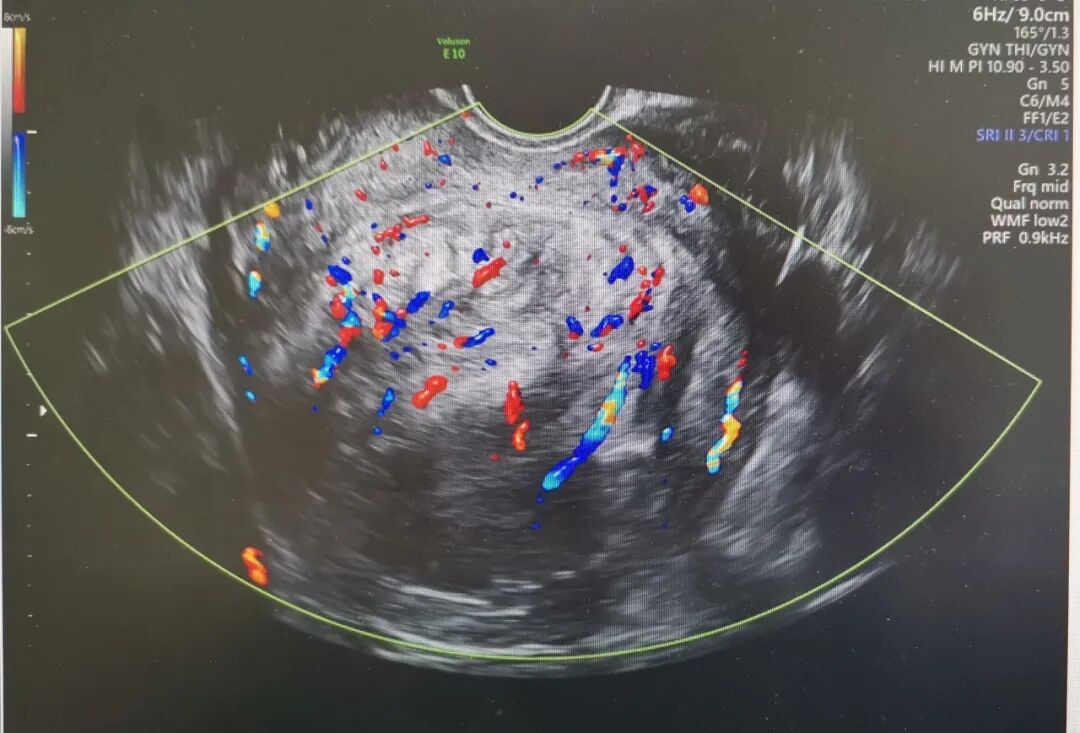

夏教授为患者安排了三维超声和宫腔镜检查,结果显示肌瘤位于宫底后壁,2-5型贯穿整个肌层,直径95mm,周边血流丰富。如果选择腹腔镜手术剔除肌瘤,子宫肌层完整性受到破坏,存在瘢痕子宫妊娠子宫破裂风险,宫腔镜手术创伤更小恢复更快,患者有生育计划,如果能通过宫腔镜手术治疗,是对生育功能最大的保护。但巨大的肌瘤马上手术,风险太大。夏教授决定先予GnRH-a类药物治疗手术预处理,缩小肌瘤体积,改善贫血后择期手术。4个月治疗后,血色素正常,宫腔镜检查显示肌瘤继续向宫腔突入,但仅稍微缩小至直径88mm,这对于宫腔镜手术仍然是个挑战。从“手术安全是第一位”的角度出发,夏恩兰主任和彭雪冰主任决定腹腔镜监护下进行宫腔镜手术,根据术中情况随时调整手术方式,“进可攻,退可守”。 术中见肌瘤突向并充满了宫腔,手术初始,宫腔可操作的空间十分有限,彭主任用娴熟的宫腔镜手术技术迅速高效切除缩小肌瘤。这一过程需要面临出血、灌流介质过度吸收综合征、子宫穿孔等重重风险。麻醉医师龚璠在手术过程中,密切关注患者生命体征为手术保驾护航。终于,在不懈的努力下,完全切除了这一巨大肌瘤,去除了导致患者大出血的元凶,也守卫了“生命宫殿”,为患者保留了生育的希望。术后患者恢复良好,顺利出院。 宫腔镜诊治中心成立32年,诊治患者数以万记计。在夏恩兰教授的引领下,宫腔镜诊治技术日益精湛,不仅保留子宫,而且保护子宫的功能,提高生育力。最初宫腔镜下子宫肌瘤切除术用于处理0、1、2型肌瘤,而现在3型、甚至2-5型的巨大肌瘤也可以通过宫腔镜手术来切除,术后2-3个月创面完全愈合,保护了生育功能,是患者的福音。 宫腔镜诊治中心在夏恩兰教授及黄晓武教授的带领下,全科医务人员齐心协力,勇于实践,精益求精,不断总结经验、提高技术,为广大患者提供更优质的医疗服务。